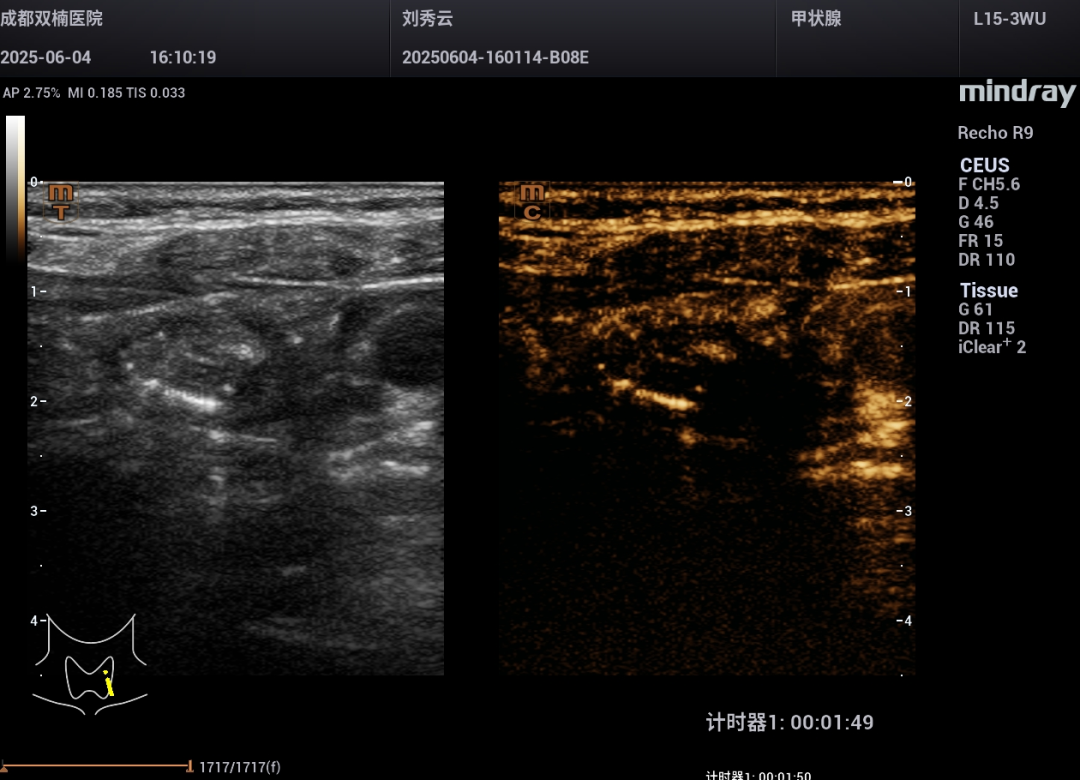

为进一步确认,程主任让刘阿姨喝下“一杯水(在400ml普通饮用水里只加了6滴造影剂)”。屏幕上清晰地显示:水流直接流入了那个“团块”里面!还发现“团块”靠近食管的部位有个小缺口。

饮造影水94秒

饮造影水109秒